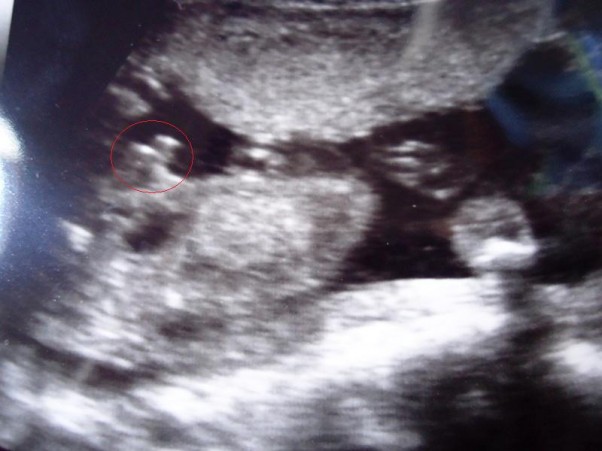

Będzie SYNUŚ!!!

Moje przeczucia mnie nie myliły. Właśnie Pani dr powiedziała aby szykować się na chłopczyka bo ewidentnie widzi znacznie więcej "między nóżkami" :)